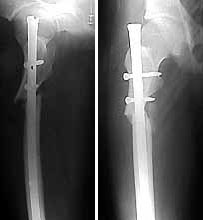

femur

The patient came to me two days after injury. Her general condition was not good with Hb 6.7 gm%. After Blood transfusions in the first stage I did standard femoral Interlocking - 10mm nail with two proximal screws. 3 days later I did Tibial and Humeral Interlocking nailing - 8mm and 6mm nail respectively with proximal locking only.

On discharge 10 days later she wass walking independently with Zimmer frame with full knee hip and shoulder movements. Xrays are attached.